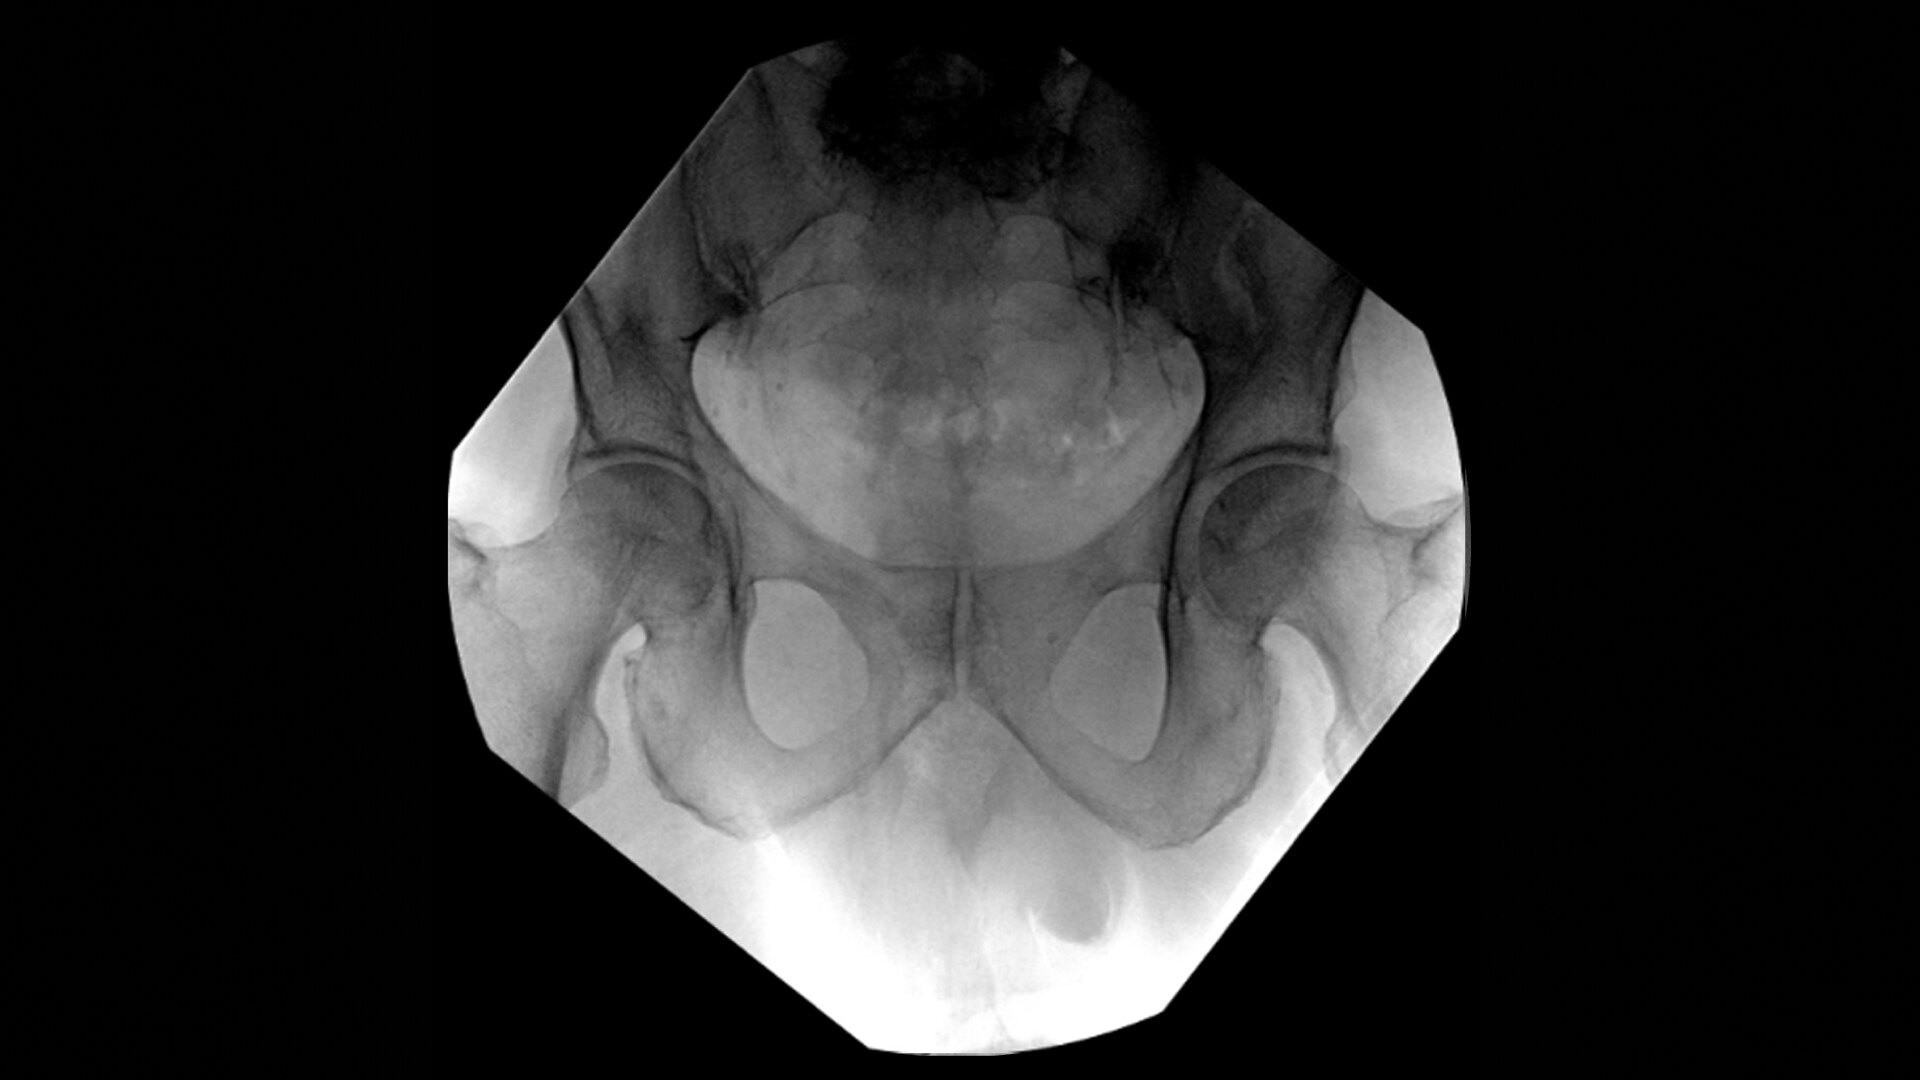

OEC C-arms provide orthopedic imaging with a large field of view optimized to clearly visualize orthopedic anatomy, such as the entire long bone femur or minute fractures in extremities. A clear display with comfortable viewing can easily show AP and lateral views, enabling efficient procedure planning.

Complex orthopedic procedures require powerful imaging systems. OEC premium C-arms perform in a variety of procedures such as:

• Hip fracture fixation

• Hip replacement